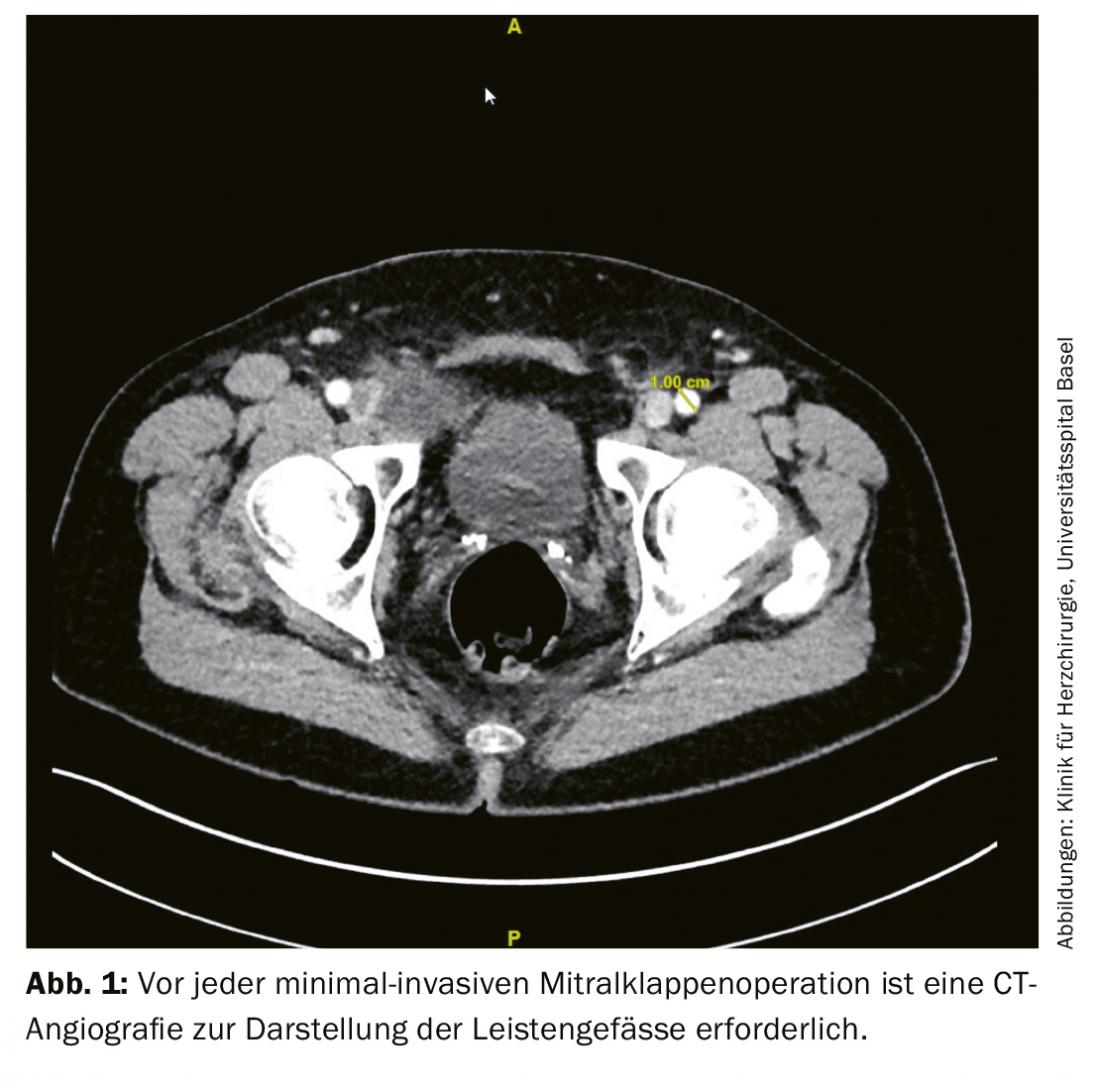

Após o consentimento do paciente, são efectuados exames pré-operatórios. Para além da ecocardiografia transoesofágica e de um grande hemograma, isto inclui uma tomografia computorizada dos coronários ou uma angiografia coronária para excluir doenças coronárias. Além disso, a sonografia duplex dos vasos do pescoço é recomendada para todos os doentes com mais de 65 anos de idade para excluir as estenoses de grau superior [7]. Para planear uma operação minimamente invasiva no coração, é também recomendado um exame tomográfico computorizado de toda a aorta até aos vasos inguinais, inclusive. Este exame descreve em particular alterações relevantes ou depósitos trombóticos da aorta, bem como vasos inguinais e possíveis aderências pulmonares (Fig. 1).